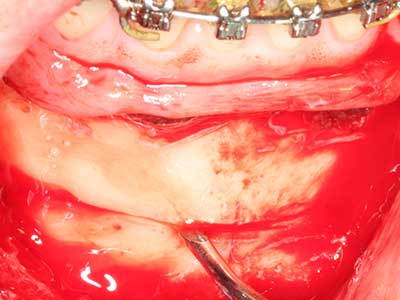

Aplicación: Partición ósea / Cortical Split

El tejido óseo no solo tiene un contenido puramente mineral, sino que también presenta una importante proporción de fibras de colágeno. Esto no solo garantiza una buena resistencia a la presión, sino también una cierta flexibilidad, que puede aprovecharse para la realización de aumentos. En la plastia de expansión clásica a efectos de una partición ósea, la cresta maxilar atrofiada se divide en su eje longitudinal y, tras alcanzar una profundidad de osteotomía suficiente, se extiende con cuidado (fig. 13-16), en un caso ideal sin desperiostizar de forma visible el maxilar (Brugnami, Caiazzo et al. 2014, Stricker, Fleiner et al. 2014). Los sistemas de tornillos y placas con distancia de expansión creciente han demostrado su eficacia para distanciar entre sí las dos tablas óseas por debajo del umbral de rotura. Por regla general, se requieren anchuras de hueso residual de al menos 3 a 4 mm (Chiapasco, Zaniboni et al. 2006) para garantizar una flexibilidad y una cobertura ósea suficientes de los implantes que van a incorporarse. En caso necesario, una osteotomía de descarga vertical unilateral o bilateral puede mejorar la flexibilidad. Como alternativa a la técnica clásica se ha descrito una combinación con otras técnicas de aumento, sobre todo en la parte bucal.

Con el uso de sierras piezoeléctricas la división se efectúa de forma especialmente cuidadosa y sin pérdidas importantes de las dimensiones, por lo que no se han encontrado diferencias significativas entre los implantes realizados en el maxilar dividido y en la cresta alveolar no deficitaria (Chiapasco, Zaniboni et al. 2006, Danza, Guidi et al. 2009). No obstante, precisamente en la partición profunda y limitada de forma local, es preciso asegurarse de que exista una adecuada irrigación por agua para evitar que se produzcan sobrecargas térmicas en las áreas de osteotomía apical.